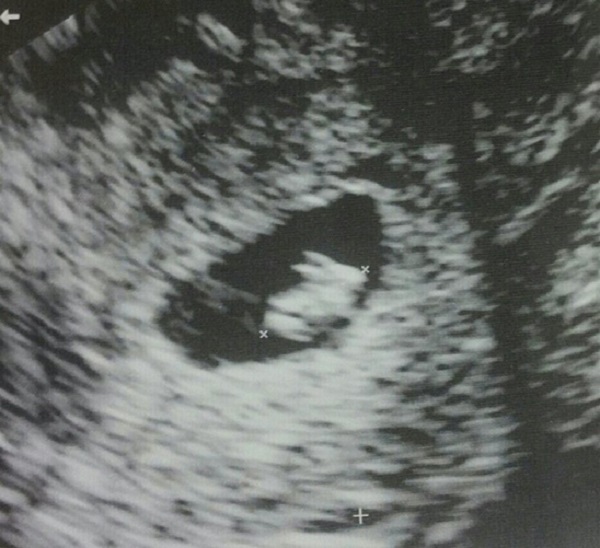

Một phụ nữ 33 tuổi hiện đang sinh sống ở bang Florida (Mỹ) đã vô cùng lo lắng khi nhìn thấy hình ảnh siêu âm của con mình. Trên màn hình siêu âm là bào thai 7 tuần tuổi, có hình dáng như một chú thỏ con đang nằm trong bụng người mẹ.

Người phụ nữ giấu tên (33 tuổi) hiện đang sinh sống ở bang Florida (Mỹ) đã vô cùng lo lắng khi phát hiện bào thai đang mang trong bụng là hình một chú thỏ có 2 tai và 4 chân sau lần đi siêu âm đầu tiên. Ngay sau khi nhận được kết quả siêu âm của mình, người mẹ sửng sốt với hình ảnh siêu âm nhận được. Cô chia sẻ bức hình này trên mạng xã hội Reddit dưới tài khoản có tên NetteFraulein và kèm theo dòng tậm trạng: “ Tôi vừa đi siêu âm lần đầu tiên, hóa ra cái thai đang mang trong bụng lại là một chú thỏ con.”

Cô chia sẻ thêm: “Trong lần siêu âm này, tôi vô cùng lo lắng vì đã từng bị mất 2 đứa con trong quá khứ. Tuy nhiên, khi thấy nhịp tim thai đang là 163 nhịp, tôi thấy yên tâm hơn. Nhưng ngay sau đó, tôi nhìn thấy hình ảnh siêu âm thì cái thai lại giống hình một chú thỏ con. Tôi cười lớn và nghĩ rằng điều này rất buồn cười.”

Hiện nay bào thai đang được 7 tuần và dự kiến em sẽ chào đời vào tháng 4 năm tới.